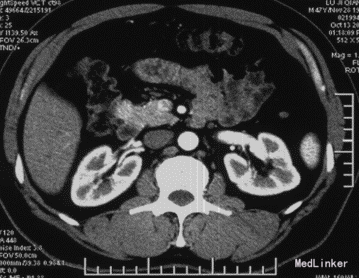

查体:神清,腹软,未及包块,无压痛及反跳痛,神经系统检查未见异常 辅查:外院头颅CT平扫:腔隙性脑梗;胰腺CT平扫:胰头、十二指肠降部稍低密度影,肝内多发小囊肿;上腹部增强CT:胰腺低密度影,考虑良性;肝内多发小囊肿。 入院检查:血、尿、粪常规、肝肾功能、电解质、凝血功能正常;AFP、CEA、CA19-9、CA125、CA15-3、CA72-4均正常;胰岛素78.33mIU/L,C肽 4.91ug/L。腹腔动脉DSA:胰头区富血供肿瘤; 胰腺增强MRI:1、胰头部富血供病变,考虑胰岛素瘤可能性大;2、肝内多发小囊肿。

术前诊断:1、胰头占位性病变(胰岛素瘤?),2、腔隙性脑梗塞,3、肝内多发小囊肿。 术后诊断:1、胰头胰岛素瘤,2、腔隙性脑梗塞,3、肝内多发小囊肿。 入院后控制血糖,完善相关检查在腹腔镜下行胰岛素瘤切除术,术中为、十二指肠、胆囊、横结肠未见异常,胆总管无扩张,打开胃结肠韧带,于胰头健可见大小约2*2cm肿块,表面光滑,边界清,突出于表面,遂行胰岛素瘤切除术超声刀沿肿块边缘完整切除肿块,检查未伤及主胰管。 术后监测血糖,行抗炎、抑酸、补液等对症支持治疗,复查C肽及胰岛素均正常,空腹血糖值正常,康复后出院。